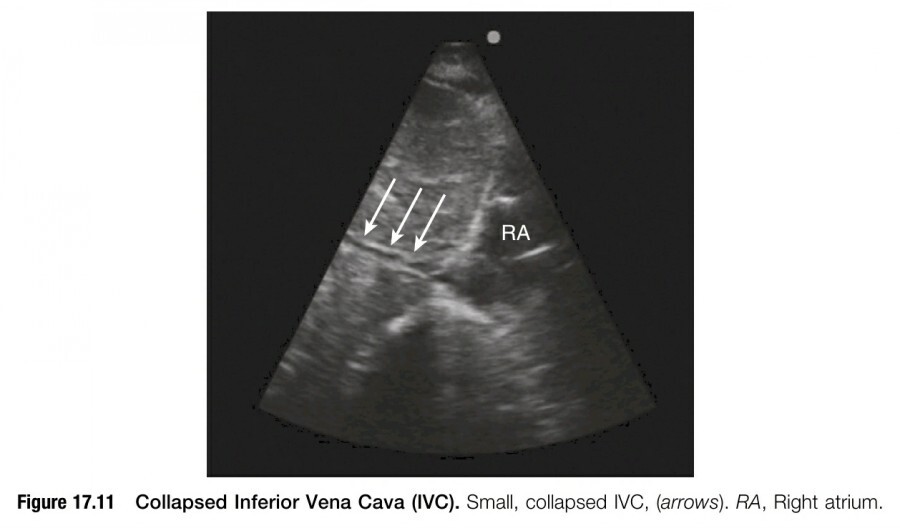

IVC diameter가 1cm 미만으로 작거나 호흡하는 동안 완전하게 collapse 되어 있다면

대부분의 환자에서는 fluid resuscitation이 임상적으로 타당할 수 있다(figure 17.11).